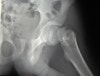

X-ray : 전자간 골절(Intertrochanteric fracture)